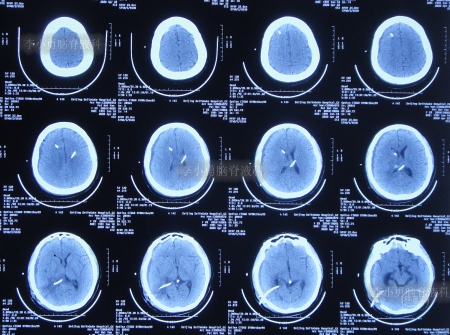

入院治疗100天即2020年7月20日,进行了脑室腹腔分流术。术后当天查头颅CT示脑室分流术后状态(图-23)。

图-23:2020年7月20日头颅CT

入院治疗109天即2020年7月29日康复出院,出院时:头晕呕吐已完全消失2月余,视物不清也变正常,睡眠也变好(图-24);出院时头颅CT示无异常(图-25)。

图-25:出院时头颅CT